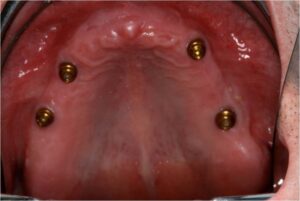

- Προσθετικη επι εμφυτευματων